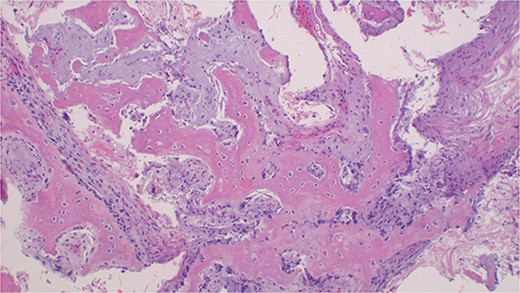

A 26-year-old male patient reported to the oral and maxillofacial unit of our institution with a chief complaint of a painless, slow-growing mass on the left side of his maxilla for three years. The lesion started as a small swelling that progressively increased in size with time, with no relieving or aggravating factors reported. There was no history of preceding trauma, loss of weight, or night sweat reported to be associated with the new growth. The patient was a non-smoker, with a healthy general condition. On examination, the patient did not have any systemic problems. There was a facial asymmetry due to the mass on his midface whose measurements were 6 by 7 cm, extending from the ala of the nose right side to the body of the zygoma bone on the same side, anterior posterior, zygomatic arch to the angle of the mouth right side, superior inferior direction (Fig. 1A). There was no enlargement of lymph nodes. Speech and swallowing remained undisturbed. On examination of the oral cavity, the mass on the maxilla, which was hard in consistency, non-tender, and measuring about 4 cm by 6 cm in its greatest dimensions, was appreciated (Fig. 1B). A clinical diagnosis of ossifying fibroma of the maxilla was considered, with a differential diagnosis of fibrous dysplasia. A CT scan of the head highlighted a well-defined expansile radiolulency mass with radiopaque features. The mass was causing bone erosion and opacification (Fig. 2A–D). Histopathology of an incisional biopsy demonstrated a benign fibro-osseous lesion composed of diffuse hyperchromatic stromal fibroblastic cell proliferation, without atypia or mitoses. The matrix was mineralized with woven and lamellar bone deposits, or cementum-like calcifications distributed throughout the lesion (Fig. 3). The diagnosis of maxillary OF was confirmed, and the treatment was scheduled.

Photomicroscopy of ossifying fibroma demonstrating a benign fibro-osseous nature of the lesion composed of diffuse hyperchromatic stromal fibroblastic cell proliferation, without atypia, or mitoses. The matrix is mineralized with woven and lamellar bone deposits or cementum-like calcifications distributed throughout the lesion, H & E staining at 200 × original magnification.